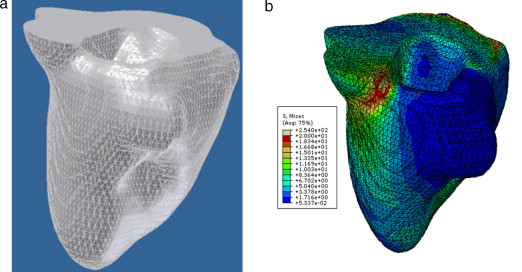

En la figura 16 se presenta el volumen final del ventrículo izquierdo con el inicio de la válvula aórtica (fig. 16 .a), el modelo final suavizado visualizado en ParaView (fig. 16 .b), el modelo en sólido visualizado en Autodesk Inventor (fig. 16 .c), el modelo en malla visualizado en GiD (fig. 16 .d) y el modelo discreto con los elementos finitos realizado con Abaqus (fig. 16 .e). Estos modelos han sido obtenidos a partir de IRM cardiovascular de un paciente con cardiopatía isquémica. Obsérvese que la protuberancia presente en la zona superior derecha del ventrículo izquierdo constituye una zona de necrosis conocida como cicatriz isquémica, la cual es alojada en el músculo del miocardio.

|

Figura 16. Vista tridimensional de ventrículo izquierdo. (a) Volumen original visualizado con ParaView. (b) Volumen original suavizado con morfología matemática visualizado con ParaView. (c) Sólido del volumen generado con Autodesk Inventor. (d) Mallado del volumen generado con GiD. (e) Modelo discreto con el método de elementos finitos generado con Abaqus empleando condiciones de contorno de prueba. |